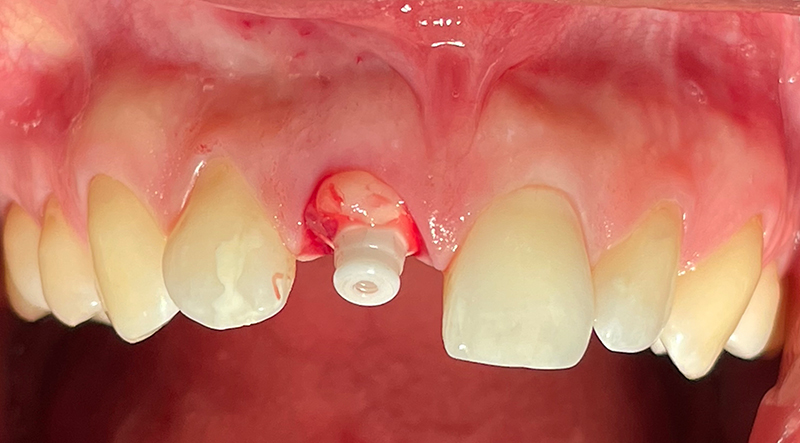

Caso 1: Un paziente, maschio di 59 anni, si presentava con cisti apicali sugli incisivi centrali e laterali mascellari con trattamento canalare inadeguato. Seguiva posizionamento immediato di impianto in ceramica SDS con carico immediato per un periodo di 2 mesi. (Fig. 1,2).

Fig. 1 (caso 1) - Radiografia panoramica pre-operatoria